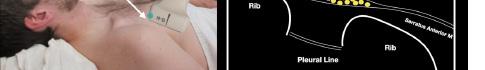

After appropriate skin disinfection, the block needle is advanced in-plane from the cephalad to caudal aspect of the patient. The needle should be advanced under clear ultrasound visualization during the entire procedure. For the Pecs I block, advance the needle to the fascial plane between the pectoralis

major and minor muscles. Hydrodissection with normal saline will confirm opening of the correct fascial plane (Image 3). Anesthetic can then be gently and slowly deposited in 2-3 milliliters (mL) aliquots to a recommended amount of 15 mL per Pecs block. It is imperative to calculate your weight-based recommended dosage of anesthetic beforehand as to prevent local anesthetic systemic toxicity (LAST). If dilution is needed, the injectate can be mixed with sterile 0.9% normal

saline. If the Pecs II block is going to be performed for axillary coverage, the needle is then advanced to the plane between the pectoralis minor and serratus anterior muscles (Image 4).

Of note, if both Pecs block I and II are being performed in a single injection, we recommend first depositing anesthetic in the fascial plane between the pectoralis minor muscle and serratus anterior muscle (Pecs II), since this can obscure the superficial structures.

Image 3. Pectoralis nerve block I injection between the pectoralis major and minor muscles: arrow on patient model indicates needle direction; the green dot indicates directional marker, and yellow dots indicate injectate within the fascial plane. Image 4. Pectoralis nerve block II injection between the pectoralis minor and serratus anterior muscles: the arrow on patient model indicates needle direction; the green dot indicates directional marker; and yellow dots indicate injectate within the fascial plane.